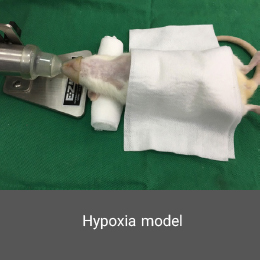

- Create and induce a variety of animal models